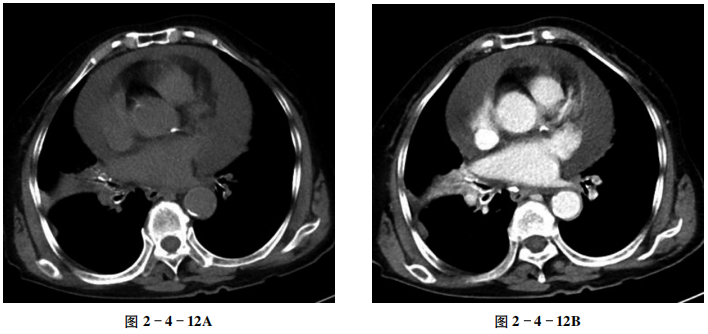

【CT征象】

心包内见大量液体密度影,密度均匀,最厚处厚度约33 mm(图2-4-12A);增强扫描无强化(图2-4-12B、C)。两下肺动脉内可见充盈缺损。

心包腔内均匀液性低密度影。

心包腔厚度增加,其内可见液体密度影;一般心包腔内厚度5~15 mm为少量心包积液,15~25 mm为中等量心包积液,25 mm以上为大量心包积液;心影可正常或增大,局部异常膨凸或成角,心缘不规则。